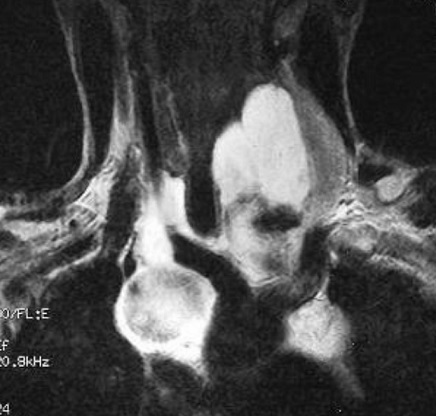

Image radiologique IRM : Aspect lesionnelle IRM est hypo à

isosignal ; rehaussement heterogene sur T1 avec Gd injection

intraveineuse ; hypersigal heterogene sur T2 avec aspect

de hyposignal en strie de cheveux du lesion